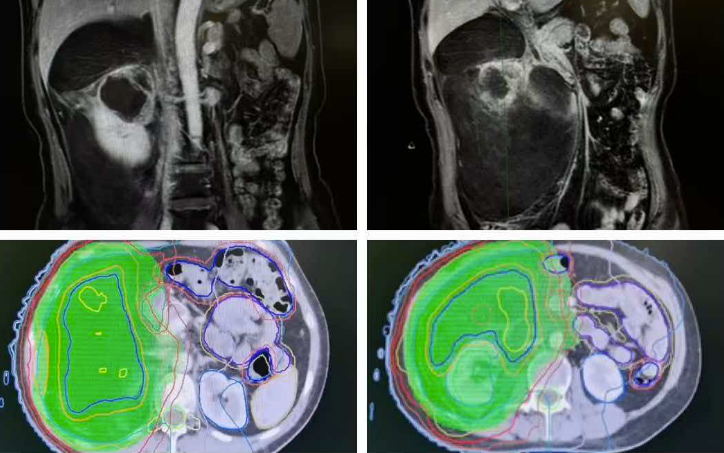

病例2:60岁女性患者,因为肚子不舒服检查,发现右侧腹膜后长了一个 25*20cm 的巨大肿瘤,已经和肝脏、膈肌、人体最粗的大血管(下腔静脉)、十二指肠粘在了一起,还出现了贫血。为了降低手术难度、减少术后复发,先穿刺确诊为脂肪肉瘤后,和放疗科卢主任团队合作,先做新辅助放疗,放疗结束1个月后,由王明帅主任团队完成肿瘤切除手术。手术中精准保护好十二指肠,把被肿瘤侵犯的部分下腔静脉壁、肝脏、膈肌一并完整切除,手术顺利完成,用时 2 个小时,出血量不到 300ml。术后半年复查,没有发现肿瘤复发。

术前腹部核磁影响和放疗区域